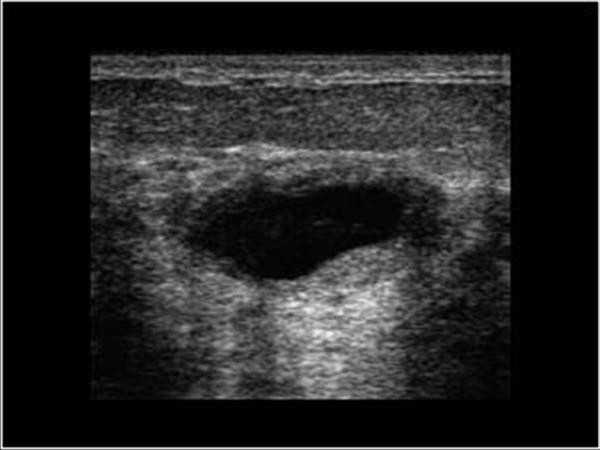

Любые новообразования в груди требуют тщательной диагностики и эффективного лечения. Фото ультразвукового исследования молочных желез позволит врачу более точно поставить диагноз и определить опасность, которую несет здоровью женщины данная киста.

В частности, одним из наиболее точных и одновременно доступных методов диагностики является ультразвуковое исследование молочных желез. Подобная процедура помогает определить количество и размеры новообразований, а также тщательно изучить особенности строения их внутренних стенок. Обязательным считается и рентгенография молочных желез (маммография), хотя оборудование для подобного обследования имеется далеко не в каждой клинике.

Киста молочной железы на УЗИ

Сразу заметим: признаки и симптомы кисты молочной железы по фото выявить невозможно. Признаки патологии выявляются с помощью УЗИ сканирования, на котором можно увидеть не только место прикрепления капсулы, но и характер ее развития и количество пораженных областей.

УЗИ сканирование опухоли

Фото УЗИ кисты молочной железы может показать, что в некоторых случаях опухоль формируется внутри мягких тканей в виде небольших жировых или твердых узелков с твердой основой и соединительными образованиями.